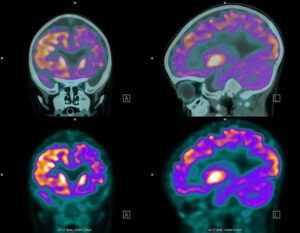

Для диагностики менингиомы используются несколько методов, позволяющих точно определить наличие и характер опухоли. Наиболее распространёнными методами являются магнитно-резонансная томография (МРТ) и компьютерная томография (КТ). Эти исследования позволяют получить детализированные изображения головного мозга и выявить опухоли. В некоторых случаях может потребоваться биопсия, чтобы понять, является ли опухоль доброкачественной или злокачественной. Даже если первоначальные результаты не подтверждают наличие менингиомы, регулярное наблюдение остаётся важным для контроля состояния пациента.